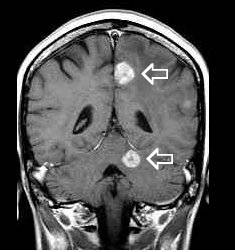

multiple (2 large mets), more multiple cases:  herehere, here, here , multiple (many small lesions) , large single met , multiple brain mets from breast cancer: patient   #1 and patient #2